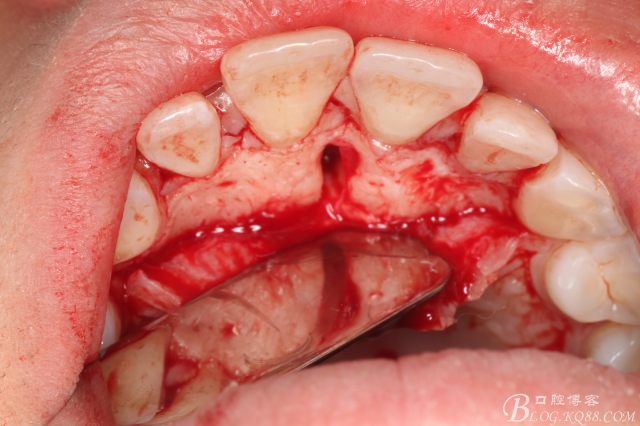

圖12.取出左邊上頜多生牙后,鼻腭管擴(kuò)大了,鼻腭神經(jīng)人那個(gè)腭側(cè)粘膜相連未斷。

圖13.去骨、暴露11腭側(cè)部分多生牙

圖14.逐漸暴露出的多生牙

圖15.用微創(chuàng)挺取出右側(cè)上腭多生牙

圖16.拔除兩顆多生牙后的鼻腭管情況